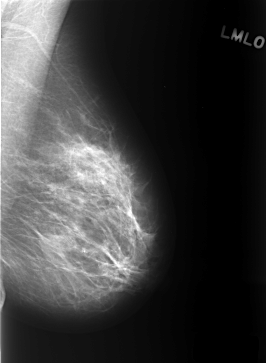

C_0402_1.LEFT_MLO

LEFT_MLO LINES 5440 PIXELS_PER_LINE 3984 BITS_PER_PIXEL 12 RESOLUTION 50 NON_OVERLAY